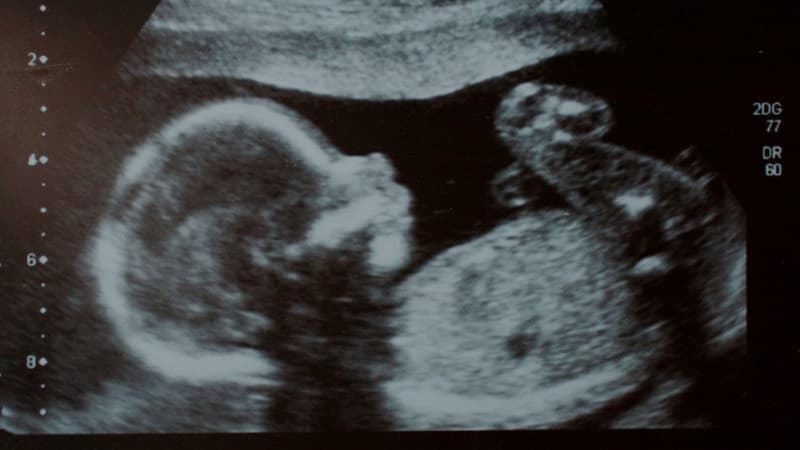

Đo nếp gấp (hay đo độ mờ da gáy) là phương pháp siêu âm nhằm đánh giá nguy cơ mắc hội chứng Down, bất thường nhiễm sắc thể và các vấn đề tim bẩm sinh. Xét nghiệm này được thực hiện để đo khoảng trống chứa chất lỏng ở lớp mô phía sau cổ của nếp gấp da gáy thai nhi.

Thời điểm thích hợp nhất để siêu âm là trong tam cá nguyệt đầu tiên, từ tuần 11 đến tuần 13 và 6 ngày của thai kỳ. Lúc này, vùng cổ của em bé vẫn còn độ trong suốt, tạo điều kiện thuận lợi cho quá trình quan sát. Bác sĩ thường chỉ định thực hiện khi chiều dài đầu – mông (CRL) của thai nhi đạt mức 45mm đến 84mm.